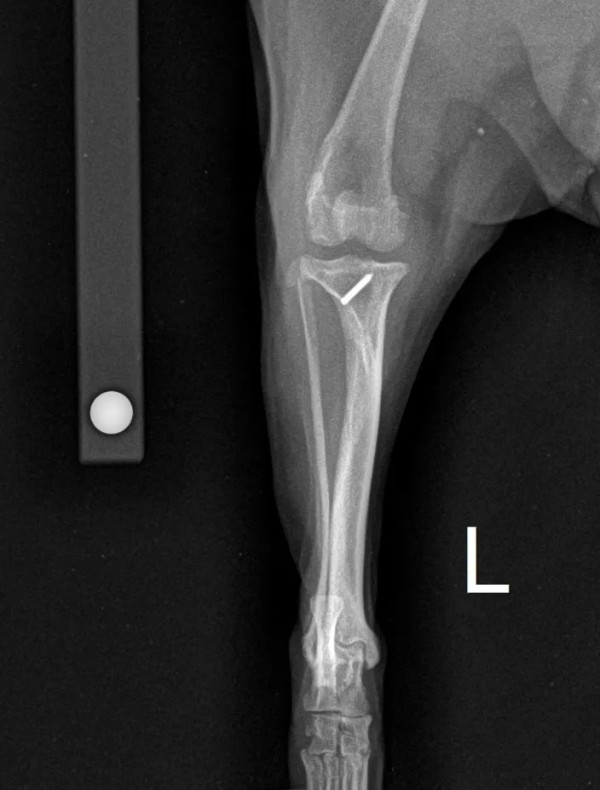

博美小乖,雌性,5.7kg,2岁

左后肢跛行一个月,有髌骨脱位病史并进行过胫骨粗隆移位手术。就诊时查体发现左后肢抽屉试验阳性,胫骨压缩试验阳性。

DR:膝关节加压,胫骨前倾。

确诊为左后肢前十字韧带断裂,进行TPLO手术治疗。

术前X光片